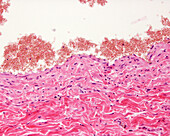

13416586 - Aorta tunica media and adventitia, light micrograph

12634941 - Aorta, tunica adventitia and media, LM

12634940 - Aorta, tunica adventitia and media, LM

12634939 - Aorta, tunica adventitia and media, LM

13756189 - Aorta, light micrograph

13742424 - Aorta wall, light micrograph